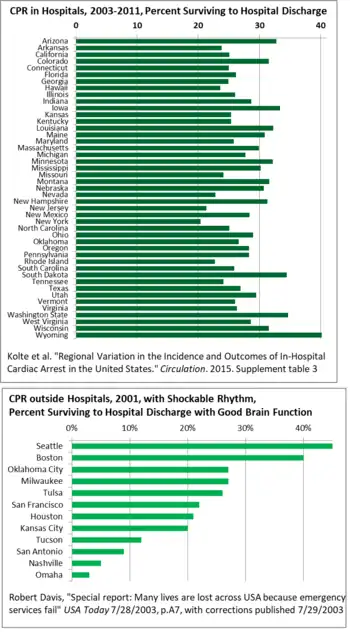

Geographically, there is wide variation state-to-state in survival after CPR in US hospitals, from 40% in Wyoming to 20% in New York, so there is room for good practices to spread, raising the averages.[132] For CPR outside hospitals, survival varies even more across the US, from 3% in Omaha to 45% in Seattle in 2001. This study only counted heart rhythms which can respond to defibrillator shocks (tachycardia).[133] A major reason for the variation has been delay in some areas between the call to emergency services and the departure of medics, and then arrival and treatment. Delays were caused by lack of monitoring, and the mismatch between recruiting people as firefighters, though most emergency calls they are assigned to are medical, so staff resisted and delayed on the medical calls.[133] Building codes have cut the number of fires, but staff still think of themselves as firefighters.

| State | Survival to Hospital Discharge |

| USA | 24.7% |

| Wyoming | 40.2% |

| Washington | 34.7% |

| South Dakota | 34.5% |

| Iowa | 33.4% |

| Arizona | 32.8% |

| Louisiana | 32.3% |

| Minnesota | 32.2% |

| Montana | 31.6% |

| Colorado | 31.5% |

| Wisconsin | 31.5% |

| New Hampshire | 31.3% |

| Maine | 30.9% |

| Nebraska | 30.7% |

| Mississippi | 30.2% |

| Massachusetts | 29.9% |

| Utah | 29.5% |

| Ohio | 29.0% |

| Indiana | 28.7% |

| West Virginia | 28.6% |

| New Mexico | 28.4% |

| Oregon | 28.3% |

| Pennsylvania | 28.3% |

| Michigan | 27.7% |

| Texas | 26.9% |

| Oklahoma | 26.6% |

| Virginia | 26.3% |

| Florida | 26.2% |

| Illinois | 26.0% |

| Vermont | 26.0% |

| South Carolina | 25.9% |

| Maryland | 25.8% |

| Kansas | 25.4% |

| Kentucky | 25.4% |

| California | 25.1% |

| North Carolina | 25.1% |

| Connecticut | 25.0% |

| Georgia | 24.9% |

| Missouri | 24.1% |

| Tennessee | 24.1% |

| Arkansas | 23.8% |

| Hawaii | 23.6% |

| Nevada | 22.8% |

| Rhode Island | 22.7% |

| New Jersey | 21.3% |

| New York | 20.4% |